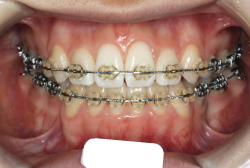

混合歯列期から治療開始した側方拡大による非抜歯症例

「配列の凸凹を治したい」という主訴で来院したケースです。診断の結果、永久歯がすべて生えそろうと、かなり厳しい叢生(歯並びの凸凹のことです)になる可能性が高いと判明しました。原因としては特に上の顎の骨が小さいため、歯を収容する容量不足になっていると診断しました。このケースの場合は、成長発育期に治療開始しますので、顎の骨を土台ごと大きくすることが可能です。

そこで、まず急速拡大装置を使用して上顎骨の拡大を行い、上顎骨の容量が拡大したことを確認後、マルチブラケット装置を使って全体の修正をする、と言う二段階の作戦をとることになりました。

この時期に使う急速拡大装置は、適切な診断に基づいて正しく使用することで確実に骨を大きくすることができます。拡大することで隙間が確保できるので、永久歯の抜歯を避けることができます。

急速拡大装置を1日1回装置の中央にある拡大ネジを、ご自身で回して頂くことで25日間くらいかけて、6mmほど拡大しました。拡大後は、上顎の前歯の隙間が広がっていることがお分かりいただけると思うのですが、土台の骨ごと広がるのでこのような隙間ができます。その後1年半くらいマルチブラケット装置を使用して、全体の修正を行いました。

結局、歯の本数を減らすことなく、すべてご自分の歯を残して正しい配列にすることができました。このケースの場合、2009年10月より拡大と経過観察を行い、2012年3月より1年2ヶ月マルチブラケット装置を装着、2013年5月に治療を終了しました。2段階で行う治療としては短期間で終了しているケースと思います。